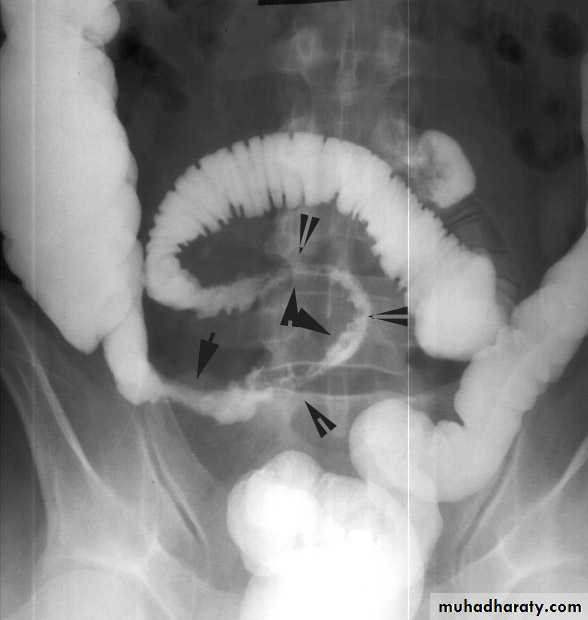

This occurs secondary to intestinal malrotationand is potentially catastrophic.less than one year old with bilious vomitingurgent surgical exloration(ladd procedure)Acute intussusception

one portion of the gut invaginates into an immediately adjacent segment.Most in children, peak five and ten months.

Causes:

- idiopathic(most common)(associated upper respiratory tract infection or gastroenteritis may precede the condition) (hyperplasia of Peyer’s patches in the terminal ileum )

leading point could be Meckel’s diverticulum, polyp, duplication, Henoch–Schönlein purpura or appendix occur in older age.

Adult cases are invariably associated with a lead point, which is usually a polyp (e.g. Peutz–Jeghers syndrome), a submucosal lipoma or other tumour.

In most children, the intussusception is ileocolic.

In adults, colocolic intussusception is more common .

Paroxysms of crampy abdominal pain (screaming)and intermittent vomiting.

Between attacks, the infant may act normally, but as symptoms progress, increasing lethargy develops.Bloody mucus (“red currant jelly ” stool) may be passed per rectum.

if reduction is not accomplished, gangrene of the intussusceptum occurs, and perforation Peritonitis

Clinical picture:

Physical examination:

- mass in the right upperquadrant or epigastrium

- absence of bowel

in the right lower quadrant (Dance’s sign).

Rarely, the apex of intussusception may pass the colon to protrude through anus

The mass may be seen on plain abdominal x-ray/US/CT (target sign) but is more easily demonstrated on air or contrast enema.

Treatment

NPO, IV fluid, IV antibioticsabsence of peritonitis radiographic(pneumatic) reduction(air/barium enema is diagnostic and curative)

Peritonitis or systemically ill child, ileoileal, pathological leading point urgent laparotomy

Reduction

(by gentle distal pressure, where the intussusceptum

is gently milked out of the intussuscipiens)

+ Non viable bowel resected

and primary anastamosis

+ Appendectomy(for ileocolic)